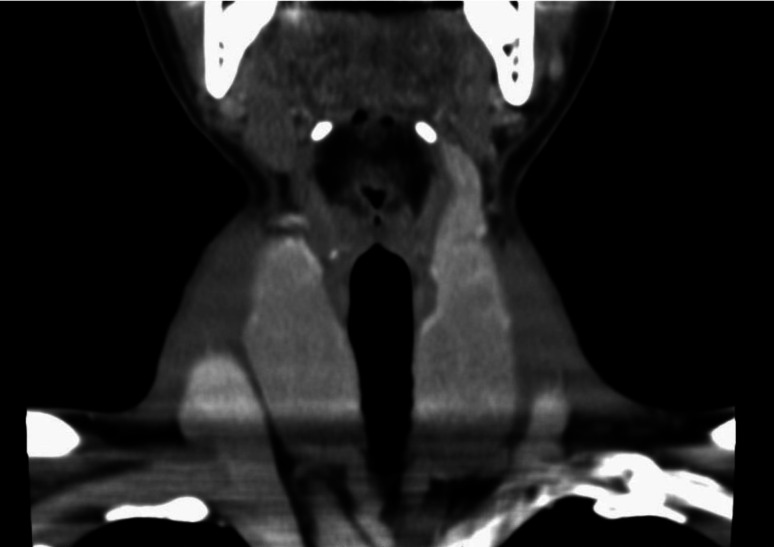

甲状腺球蛋白基因异常导致甲状腺激素生成障碍。6岁男童,近亲父母,甲状腺肿大,轻度甲状腺功能减退(促甲状腺激素[TSH] 7.2 μIU/mL,游离T3 [FT3] 3.4 pg/mL,游离T4 [FT4] 0.6 ng/dL)。尽管给予左旋甲状腺素(LT4)和正常的TSH水平,甲状腺肿进展缓慢,在青春期开始时迅速增大。甲状腺显像显示123I摄取量高达75.2%,血清甲状腺球蛋白水平为13 ng/ml,与甲状腺肿大不成比例地低。DNA序列分析发现了一种新的纯合子错义变异,c434g > a [p]。gly145 [glu],在甲状腺球蛋白基因中。增加LT4剂量可抑制甲状腺肿的生长。17岁时行甲状腺切除术。甲状腺组织的甲状腺球蛋白分析检测到内质网中存在突变的甲状腺球蛋白,表明Gly145Glu变异体损害了甲状腺球蛋白从内质网到高尔基体的运输。在临床过程中,FT3/FT4比值升高,甲状腺肿大。高FT3/FT4比率和甲状腺肿似乎是对激素合成受损的代偿反应。甲状腺球蛋白缺陷伴甲状腺肿应使用LT4治疗,即使TSH水平正常。

Thyroglobulin gene abnormalities cause thyroid dyshormonogenesis. A 6-yr-old boy of consanguineous parents presented with a large goiter and mild hypothyroidism (thyroid-stimulating hormone [TSH] 7.2 μIU/mL, free T3 [FT3] 3.4 pg/mL, free T4 [FT4] 0.6 ng/dL). Despite levothyroxine (LT4) administration and normal TSH levels, the goiter progressed slowly and increased rapidly in size at the onset of puberty. Thyroid scintigraphy revealed a remarkably high 123I uptake of 75.2%, with a serum thyroglobulin level of 13 ng/ml, which was disproportionately low for the goiter size. DNA sequencing revealed a novel homozygous missense variant, c.434G>A [p.Gly145Glu], in the thyroglobulin gene. Goiter growth was suppressed by increasing the LT4 dose. Thyroidectomy was performed at 17-yr-of-age. Thyroglobulin analysis of the thyroid tissue detected mutant thyroglobulin present in the endoplasmic reticulum, demonstrating that thyroglobulin transport from the endoplasmic reticulum to the Golgi apparatus was impaired by the Gly145Glu variant. During the clinical course, an elevated FT3/FT4 ratio was observed along with thyroid enlargement. A high FT3/FT4 ratio and goiter seemed to be compensatory responses to impaired hormone synthesis. Thyroglobulin defects with goiter should be treated with LT4, even if TSH levels are normal.